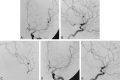

27-year-old man with hemiplegia and aphasia associated with a left parietal lobe hemorrhage who was found to have an aneurysm of the middle cerebral artery (MCA). A and B, Anteroposterior (A) and lateral (B) views of a left internal carotid arteriogram show an aneurysm on the posterior parietal branch of the left MCA. C, A selective MCA arteriogram (lateral view) better shows the aneurysm and the small branch from which it arises. D and E, Anteroposterior (D) and lateral (E) views of a left internal carotid arteriogram after occlusion of the parent vessel no longer show the aneurysm. The aneurysm was trapped by using two 2 × 10-mm coils and 2-mm straight coils.

39-year-old man with sudden onset of severe headaches, nausea, and vomiting who was found to have subarachnoid hemorrhage and an aneurysm of the left superior cerebellar artery (SCA). A, Left vertebral arteriogram (anteroposterior view) shows a small aneurysm on a hemispheric branch of the right SCA. B, Selective right SCA arteriogram (anteroposterior view) better shows the aneurysm. C, Postprocedural right SCA arteriogram (anteroposterior view) shows occlusion of the hemispheric branch and the aneurysm. Five 2-mm straight coils were used for occlusion. Note some retrograde filling of the occluded branch. D, Left vertebral arteriogram (anteroposterior view) obtained 3 months after coil occlusion shows the aneurysm remains occluded.